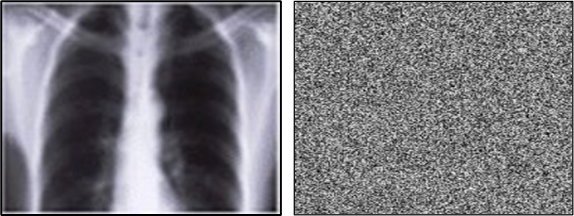

Image source: Bano M, Habib U, Iqbal J, Malik H, Ullah I 2026

Computer scientists have developed a breakthrough way to encrypt medical images such as X rays, CT scans and MRIs, keeping them secure even if hospital networks are breached. Their method is published in the Wiley Journal of Computational and Mathematical Methods.

Medical imaging systems have been repeatedly identified as weak points, with many relying on legacy protocols that were never designed to be exposed to the internet, making image level encryption an urgent priority. Developed by researchers at UEA in collaboration with international partners, the new encryption approach uses advanced mathematical techniques to make each protected image uniquely unpredictable and extremely difficult to hack, while still fast enough for everyday NHS use.

Image level encryption changes the situation entirely. Even if attackers breach a server, intercept a transfer, or access a PACS archive, the images remain unreadable without the key. Jawaid Iqbal, Associate Professor at Riphah International University, Pakistan, said: “This approach helps keep private medical details safe and limits the damage hackers can cause if they get into hospital systems. The process meets modern expectations for data security and adds an extra layer of protection, even when older equipment or external suppliers create risks.”

Chaotic mathematics (chaos theory) describes systems that follow simple rules but react so strongly to tiny changes that their outcomes look completely random. The ‘Butterfly Effect’ is an example of this, where wingbeats in one place can cause a hurricane in others.

Dr Malik said: “Because of this extreme sensitivity, chaos creates patterns that appear unpredictable, which is why it’s useful in encryption, turning data into something that looks random and is extremely hard to reverse without the exact key. A major limitation of previous research solutions is speed - many are too slow for real time clinical use. Our new method is expressly engineered for NHS environments and can encrypt and decrypt images in around two-to-four seconds.”

The chaos-theory-based encryption uses systems that behave in extremely unpredictable ways - making it hard for hackers to guess how an image is being scrambled, using techniques such as:

- S-Boxes: special tables that decide how parts of the image are substituted during encryption. Because these S Boxes change each time, attackers can’t rely on fixed patterns to break the code.

- Galois Field arithmetic: a type of mathematical system often used in cryptography. This helps mix and transform the image data in precise but very hard to reverse ways.

- XNOR diffusion: a process that blends each pixel’s data with its neighbours. This ensures that even tiny changes ripple across the whole image, hiding any recognisable structure.